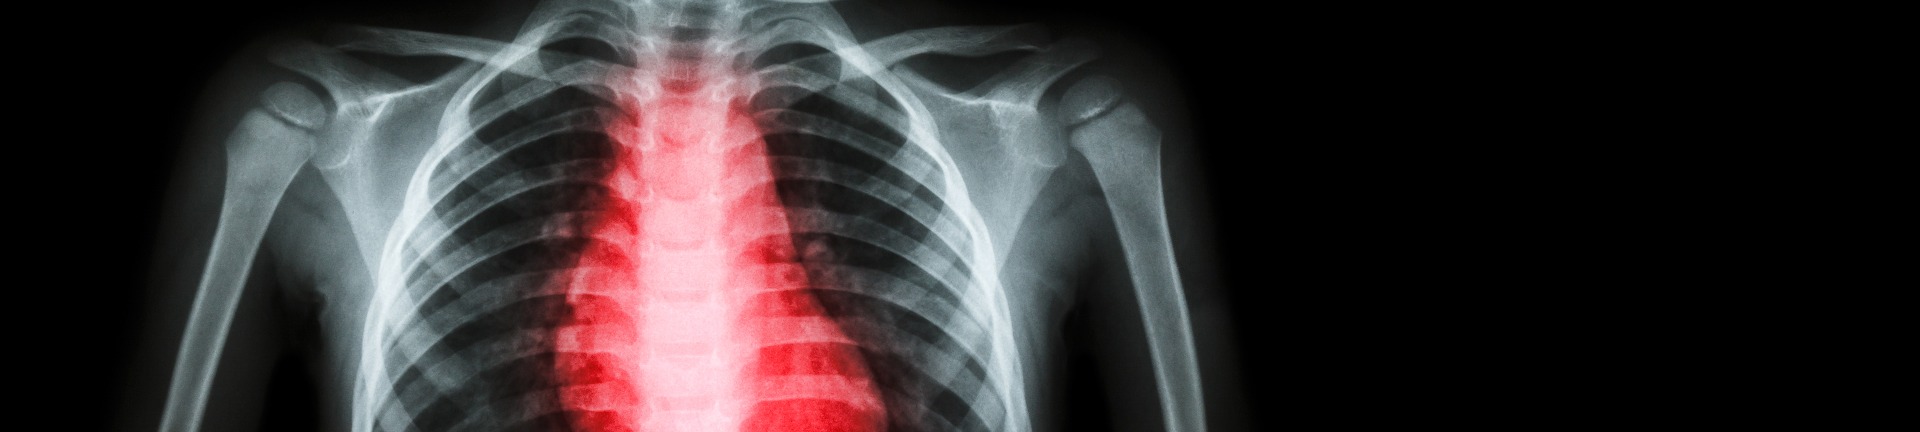

Determining the health and economic burden of rheumatic heart disease in Australia

How rheumatic heart disease affects our population and health system, and approaches/strategies to lessen the burden

This National Health and Medical Research Council-funded project looks at the burden and outcomes of rheumatic heart disease (RHD) in Australia’s population and healthcare system. Through the group’s research, we aim to provide key evidence to underpin policy recommendations to end RHD in Australia.